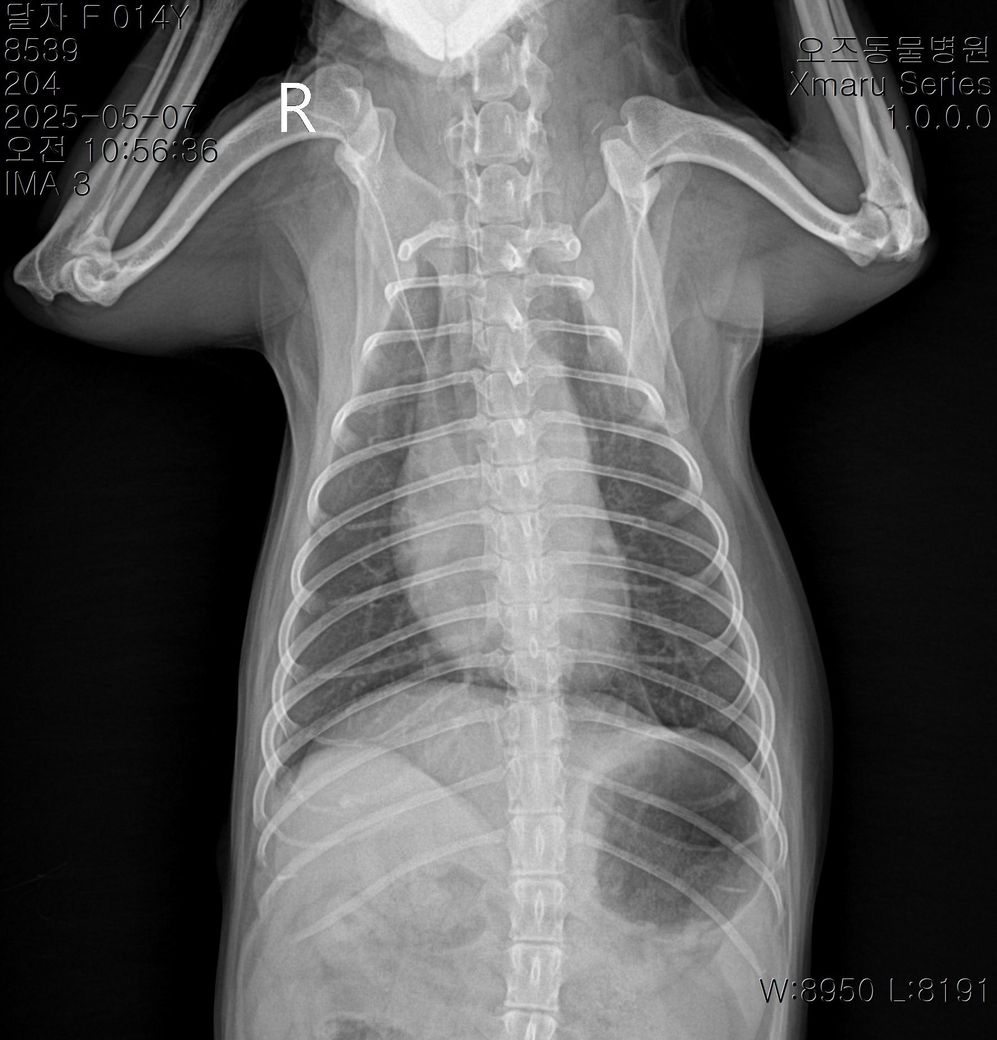

그리고 이번에 찍은 엑스레이 사진 판독으로 현재 어떤지 봐주시겠어요

아래사진이 현재구요

현재사진은 세번째 다른병원에서 찍은 사진입니다